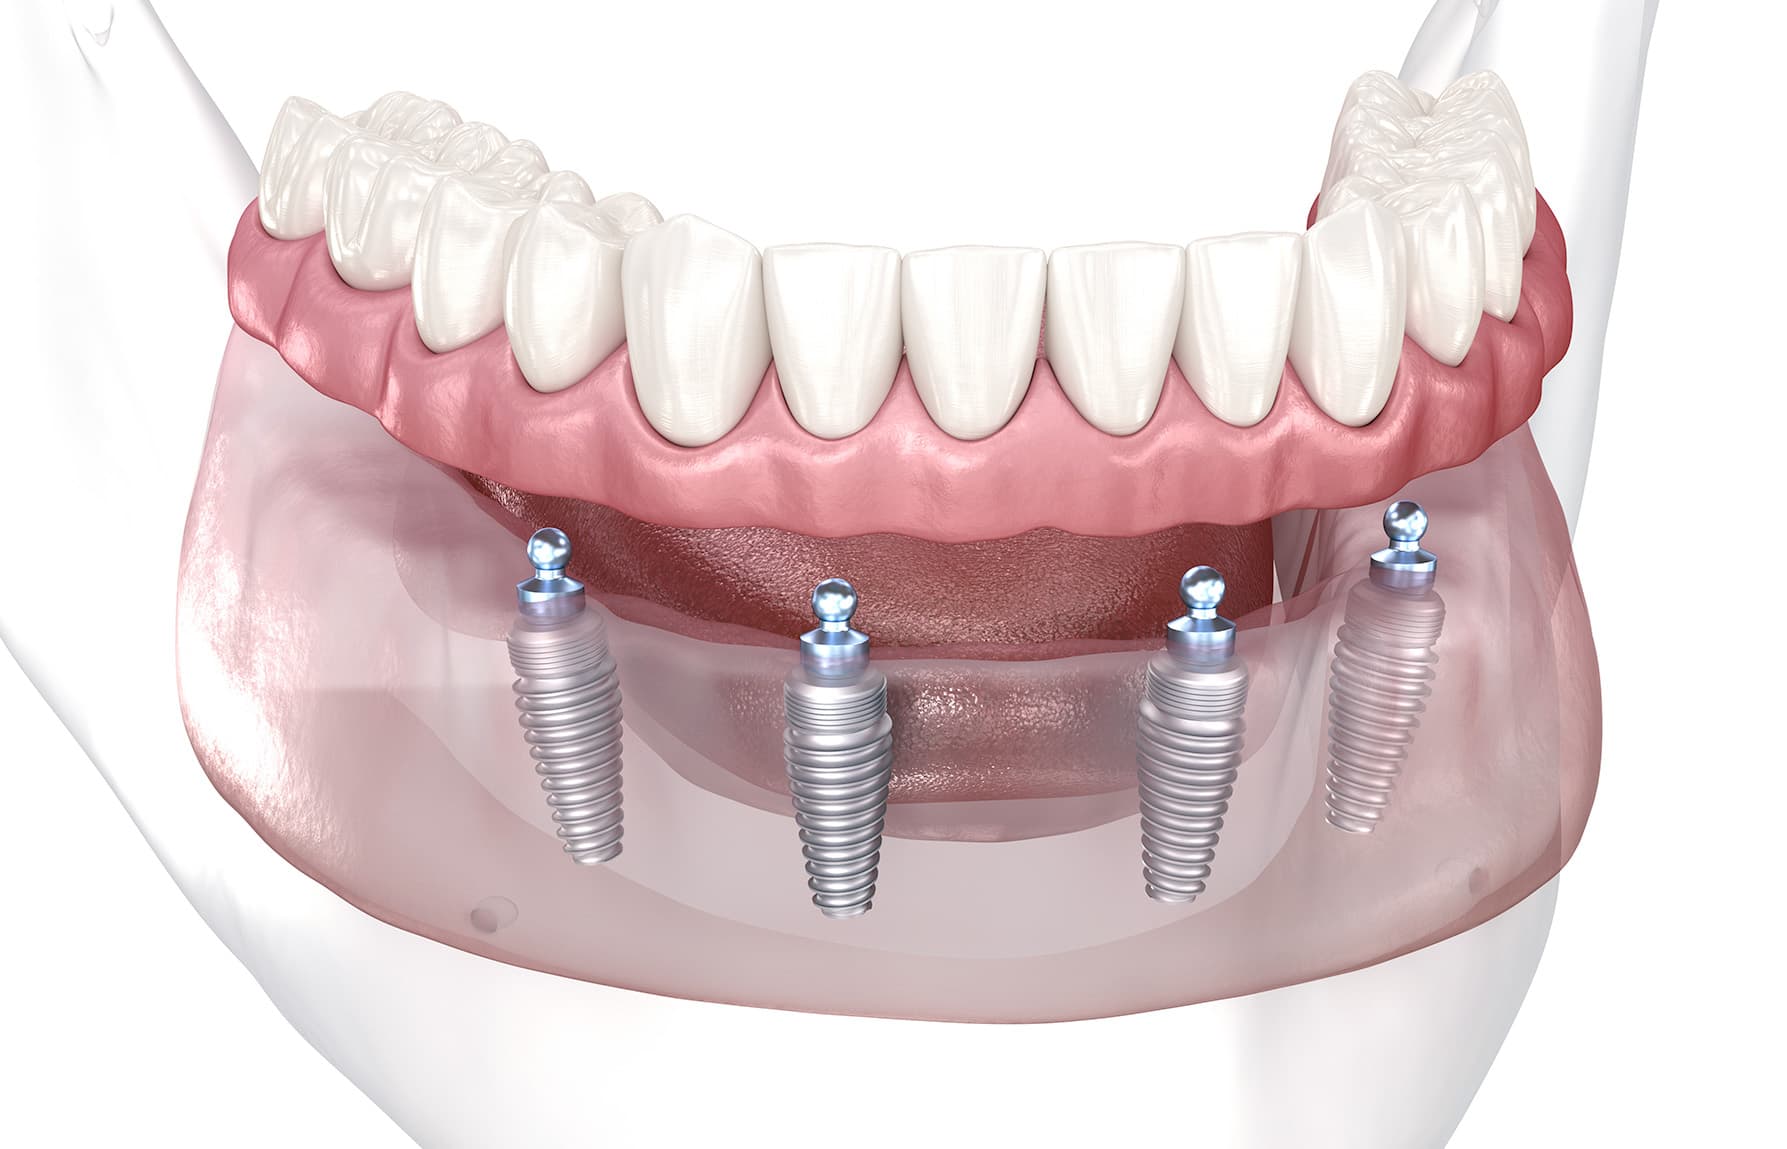

Edentaat (geen tanden en kiezen)

Wanneer er geen tanden en kiezen meer in een kaak zitten, is er sprake van een edentate (tandenloze) kaak. Door slinken (resorbtie) van de kaken op termijn wordt de houvast van gebitsprothesen steeds slechter.

In de bovenkaak is dat probleem vaak minder groot dan in de onderkaak. De onderkaak is met gewrichten aan de schedel verbonden en is daardoor beweeglijk. Bij openen van de mond, aanspannen van de spieren en beweeglijkheid van de tong komt de onderprothese gemakkelijk van zijn plaats, zeker als de houvast door het slinken van de kaak verloren is gegaan.

Door twee implantaten in de onderkaak aan te brengen kan er houvast worden verkregen door drukknoppen of een stegverbinding. Bij deze laatste constructie worden de implantaten met elkaar verbonden door een metalen staaf. Aan de binnenkant van de overkappingsprothese bevinden zich klemmen die de prothese op hun plaats houden. Men noemt dit ook wel een klikgebit.

Ook in de bovenkaak is het mogelijk een klikgebit te maken. Doordat dit gebit zijn houvast ontleent aan implantaten, is het mogelijk de constructie zo te maken dat er geen bedekking van het gehemelte is. Dit is een groot voordeel omdat de smaakgewaarwording zo behouden blijft.